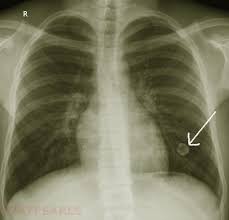

A description of popcorn calcification—meaning images that look like popcorn on a ct. Eccrine angiokeratomatous hamartoma combined with solitary angiokeratoma or verrucous venous malformation: Residents and fellows contest rules | international ophthalmologists contest rules. Endobronchial hamartoma resected by rigid bronchoscope. Report of two cases and comprehensive review of the literature.

A large hamartoma of the spleen. Multiple hamartomas throughout the body occur in cowden's disease. A description of popcorn calcification—meaning images that look like popcorn on a ct. Endobronchial hamartoma resected by rigid bronchoscope. A mass resembling a tumor that represents anomalous development of tissue natural to a part or organ rather than a true tumor. Most isolated hamartomas are benign but in cowden's disease there is a risk that one or more may undergo malignant change.4. High magnification shows the 3 components of fhi. Report of two cases and comprehensive review of the literature.

Hamartoma is a benign (not cancer) growth made up of an abnormal mixture of cells and tissues normally found in the area of the body where the a lesion first described by german pathologist eugen albrecht in 1904, hamartomas are generally benign tumors that may occur in the lungs, skin. A description of popcorn calcification—meaning images that look like popcorn on a ct. The hamartoma can occur in almost any organ and is usually asymptomatic. High magnification shows the 3 components of fhi. In radiology, hamartomas often mimic malignancy. Jump to navigation jump to search. Is that hamartoma is (pathology) a benign mass of disorganized tissue while teratoma is (pathology) a benign or malignant tumour, especially of the gonads, that arises from germ cells and consists of different types of tissue such as skin, hair, or muscle. When located on the skin, especially the face or neck, they can be extremely disfiguring, as.

A description of popcorn calcification—meaning images that look like popcorn on a ct. High magnification shows the 3 components of fhi. A hamartoma is a focal malformation that resembles a neoplasm in the tissue of its origin. The hamartoma is the dark circular object on the left that dominates the image. A large hamartoma of the spleen.